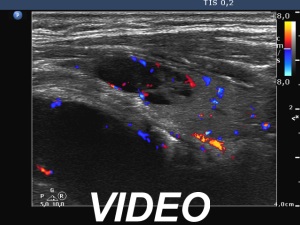

Ultrasonography. The right lobe was extremely enlarged with the dimensions of 50, 50 and 85 mm, depth, width and length, respectively. This lobe was composed of multiple hypoechoic areas within an echonormal background. The left lobe also had a hypoechoic lesion.